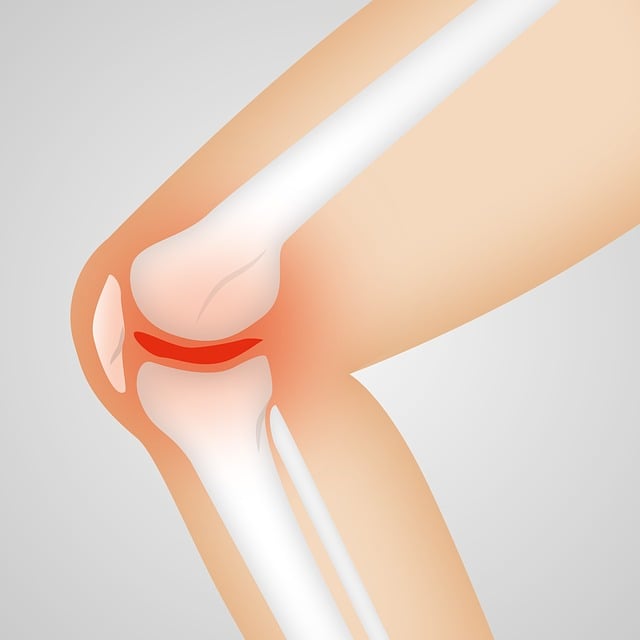

무릎통증 원인, 단순한 통증이 아닌 구조적 문제

무릎 통증의 대표적인 원인은 다음과 같다.

- 퇴행성 관절염: 연골이 닳아 관절 간 마찰이 증가하면서 통증 유발. 50대 이후 여성에게 흔하다.

- 반월상 연골 손상: 스포츠나 외부 충격으로 발생하며, 무릎이 ‘잠기는 느낌’과 함께 통증이 나타난다.

- 십자인대 파열: 격한 운동 중 무릎이 꺾이거나 돌아가면서 발생. 부기와 관절 불안정성이 동반된다.